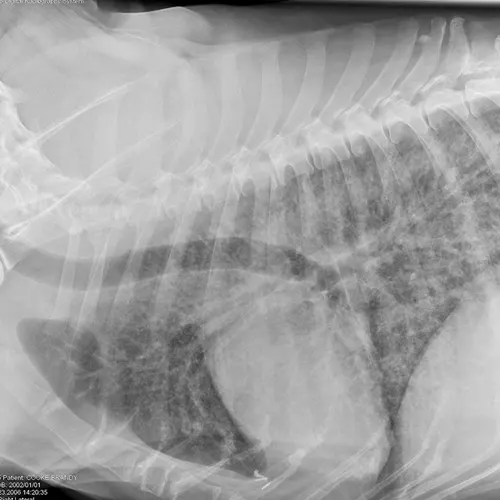

Eosinophilic bronchopneumopathy (EB) is an idiopathic inflammatory hypersensitivity disorder associated with acute onset coughing, gagging, retching, and/or respiratory distress. Radiographs may reveal a diffuse bronchointerstitial pattern or alveolar disease (Figure 3). Patients with EB have airway cytology supportive of eosinophilic inflammation and are negative for parasitic testing.

FIGURE 3

Eosinophilic bronchopneumopathy. Note the heavy, patchy bronchointerstitial pattern.